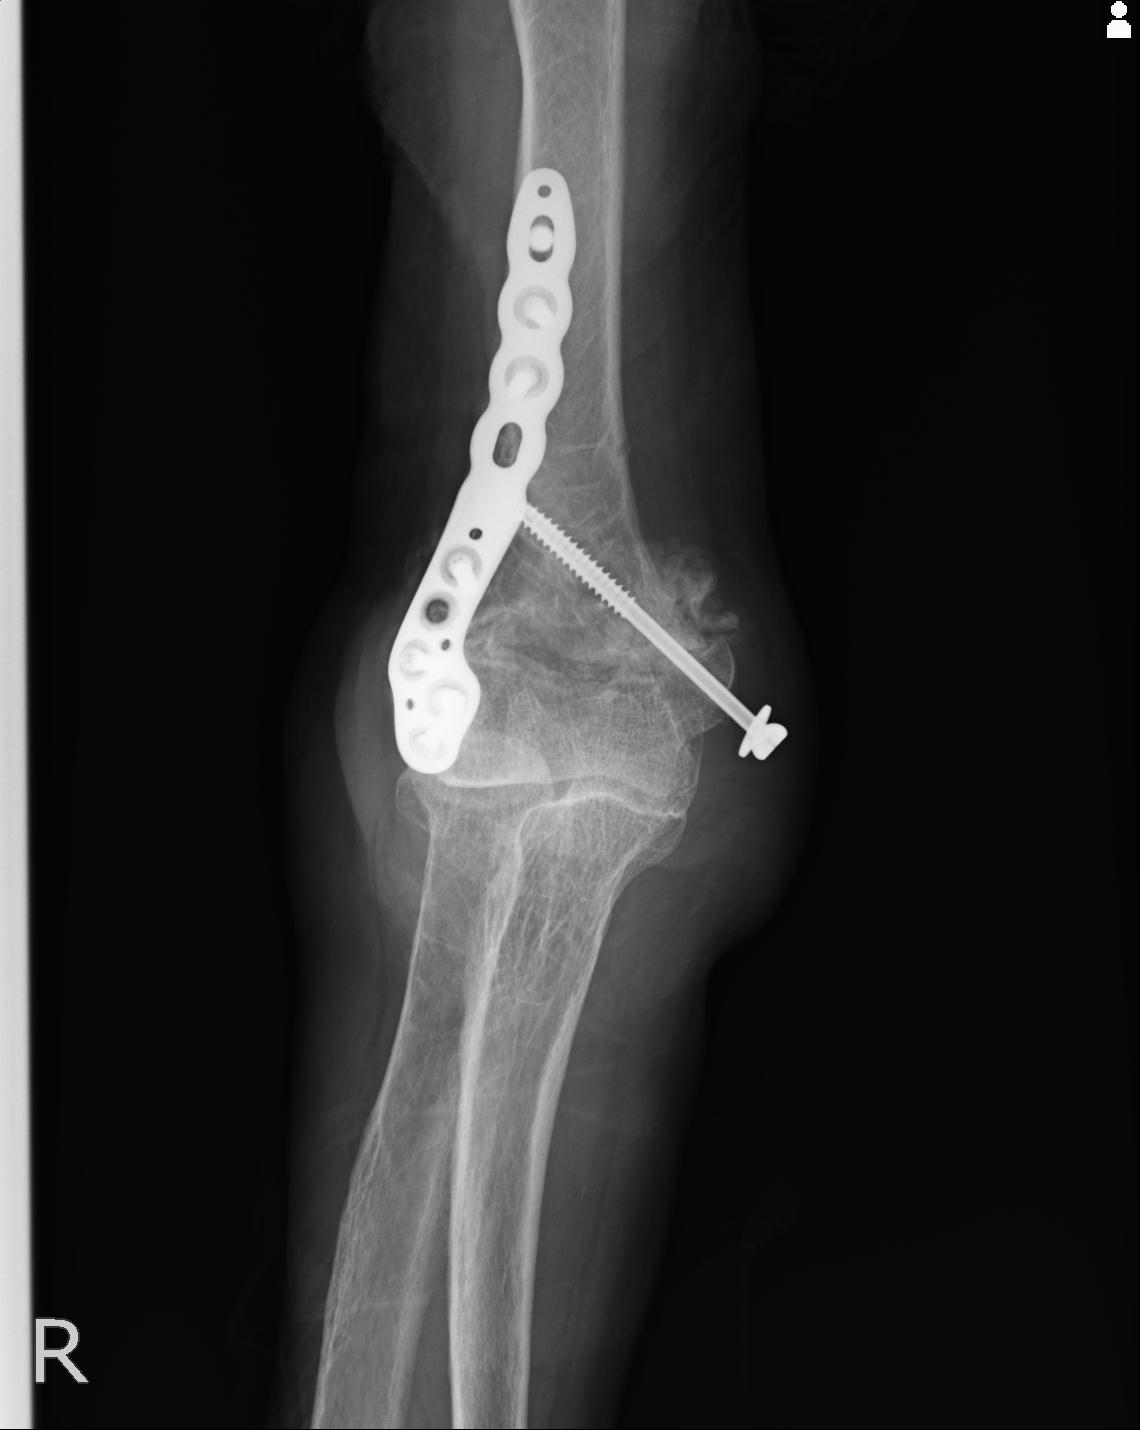

56476 8/28 4R 1/21 2R 左足関節 デジカメ写真 72歳女性 右足関節AS